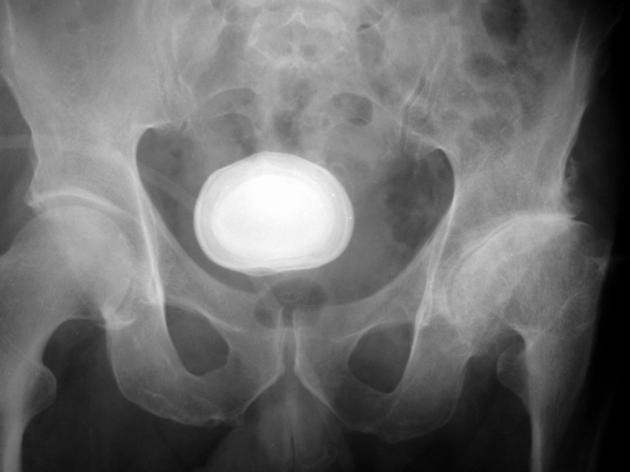

• Batu ginjal atau batu kandung kemih. Kondisi ini terjadi karena pembentukan kristal dari mineral tertentu. Kristal akan membesar seiring waktu dan menjadi batu keras. Pada awalnya batu ini tidak menyebabkan nyeri, hingga menyumbat aliran urine. Nyeri kolik terjadi bila ada batu yang tersangkut. Kondisi ini menyebabkan hematuria yang dapat dilihat dengan mata telanjang maupun saat pemeriksaan laboratorium.

• Tes radiologi. Pemeriksaan ini meliputi USG, CT Scan, atau MRI. Tujuan pemeriksaan ini untuk melihat kelainan seperti batu ginjal, tumor, atau kelainan lain.